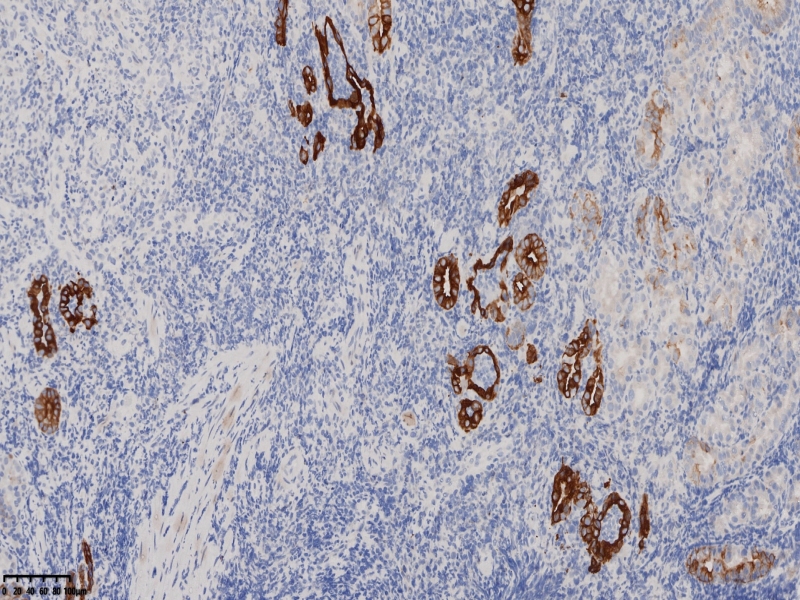

CK7

布),符合局灶黏膜内癌变(牵手癌);KI67:60%,CK7:部分+,CK20:表层腺体+,MUC5:

30%,MUC6:60%+,Villin5%,CDX-2 -,p53 60%,CEA 10%, SYN 散在+,10%;